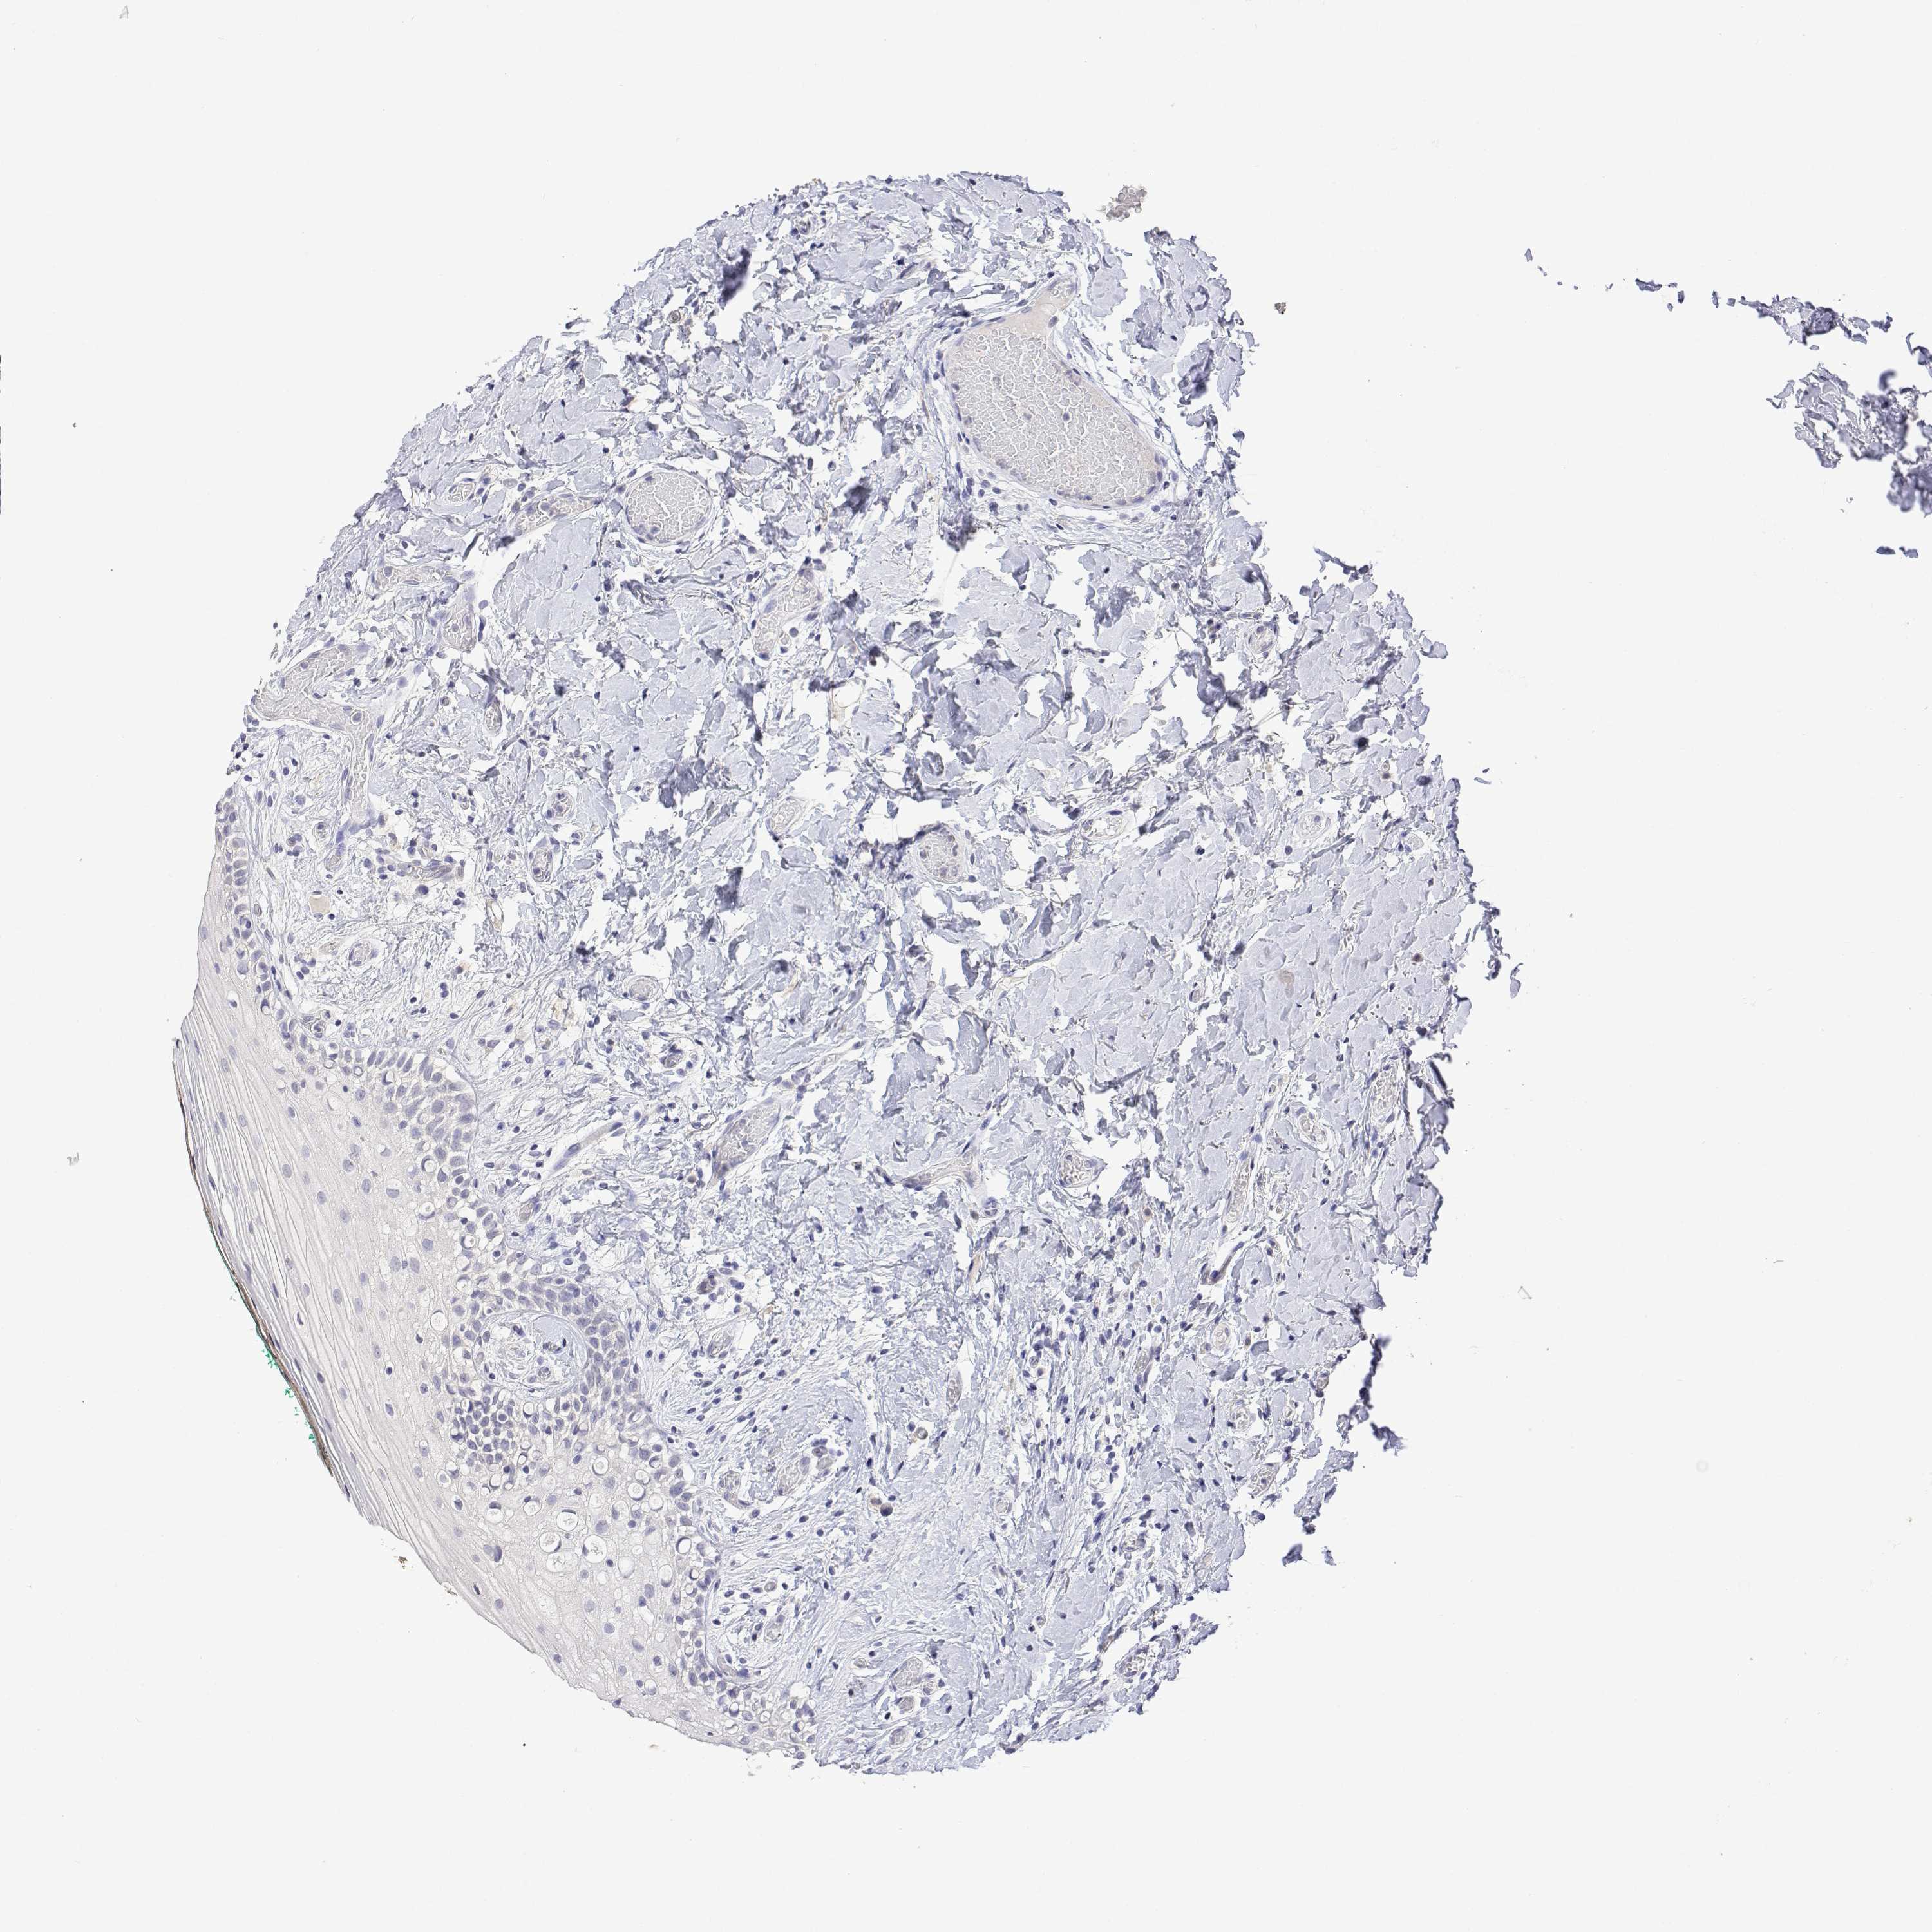

PLCB1